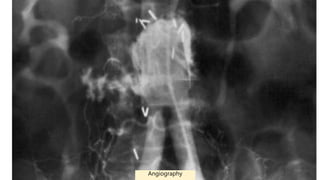

• Angiography : The angiography detection rate for AEF is 26%

CT scanEGD

• #28 aortoenteric fistula arising from the proximal anastomosis of a bifurcated aortic prosthesis. and the contrast material filling-in the bowel lumen. Angiography is useful in planning reconstruction after graft excision but will only rarely document an aortoenteric fistula because most stable patients will have an occlusive thrombus sealing the fistula